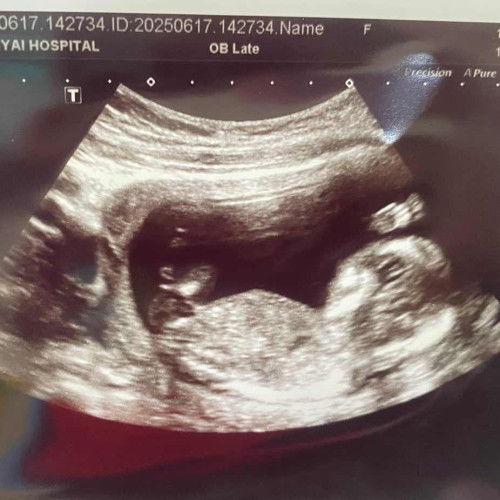

รูปภาพซาว์ดูเพศ

น้องผญ หรือ ผช ค่ะแม่ๆ ช่วยดูหน่อยค่ะ ดูไม่ออก🥰#ขอบคณสำหรับคำตอบล่วงหน้านะคะ